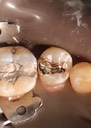

Joe Cha #3 casting on model